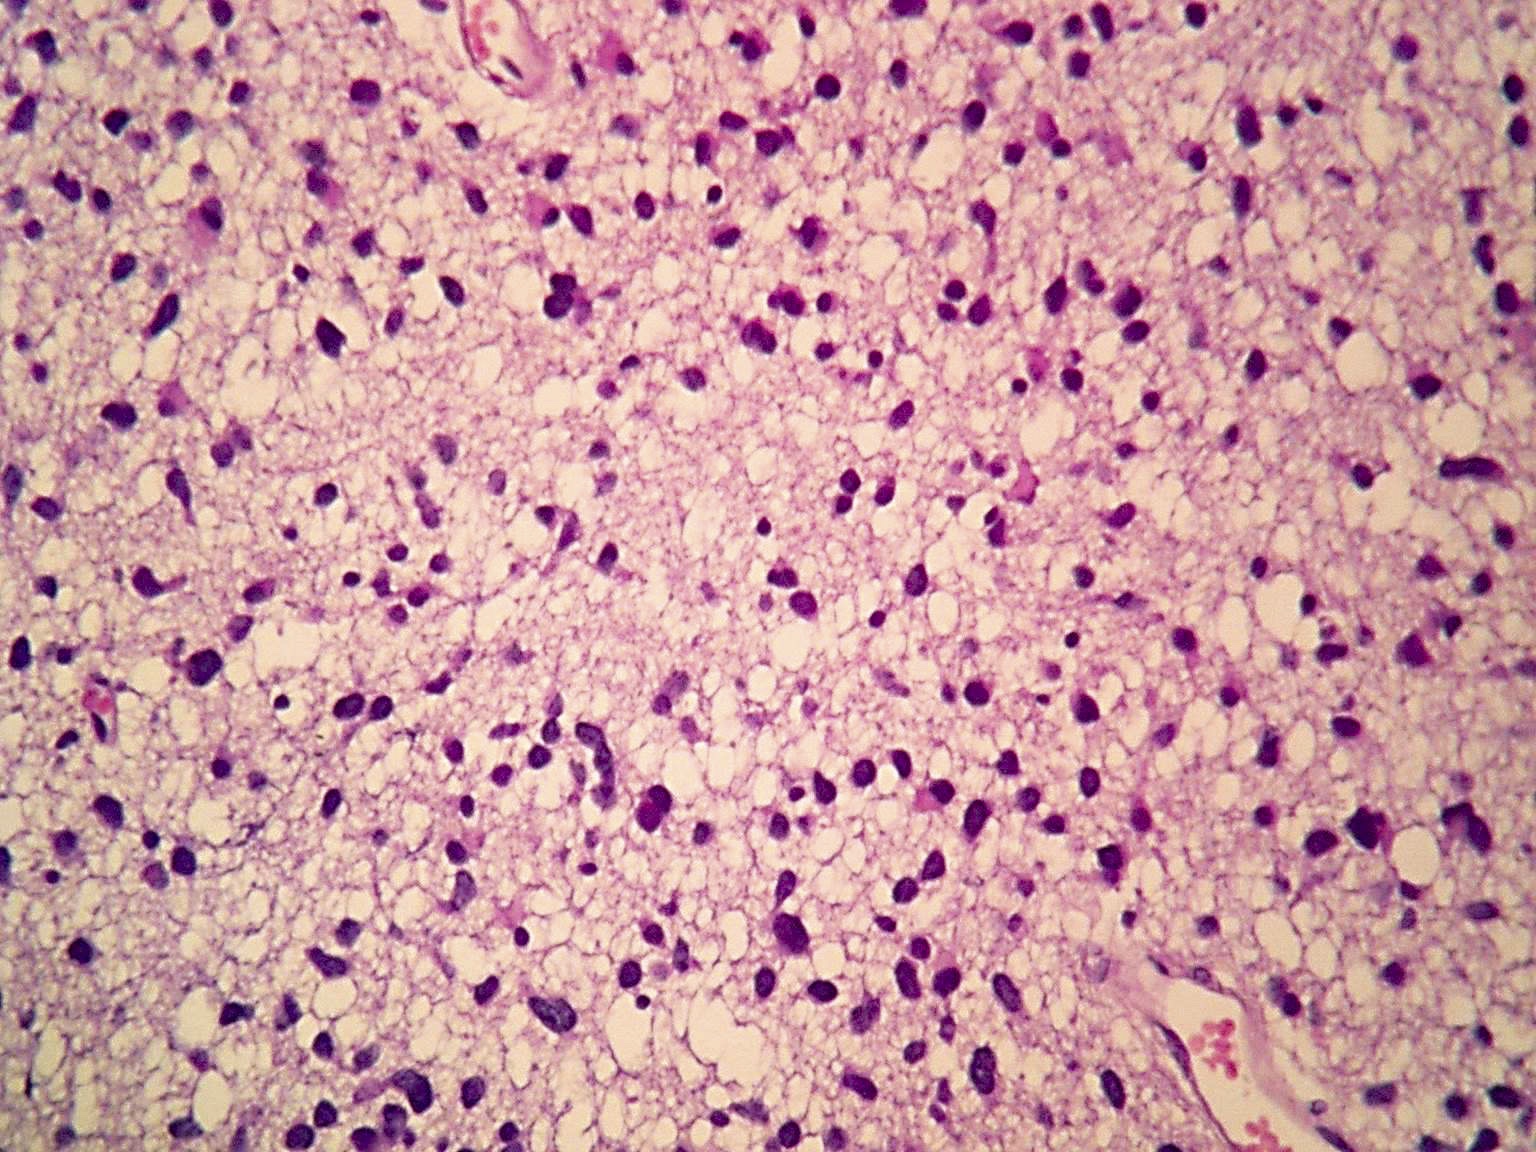

Microscopic (histologic) description

- Diffusely infiltrating tumor cells with oval to elongated astrocytic nuclei and varying appearance of tumor cytoplasm and fibrillar glial processes (Acta Neuropathol 2015;129:789)

- At the periphery, tumor cells may infiltrate in a diffuse single cell pattern, often with entrapped neurons and axons

- Cellular morphology is variable, even within a single tumor

- Commonly there is a mix of cells with elongated nuclei and fine fibrillar processes, cells with eccentric nuclei and glassy eosinophilic cytoplasm (gemistocytes), larger pleomorphic cells and small cells with scant cytoplasm

- May show oligodendroglioma-like areas

- Myxoid background and microcyst formation may be present

- Variable mitotic activity, cellularity and nuclear atypia depending on CNS WHO grade

- In small biopsy specimens, the presence of 1 mitosis may be sufficient for a CNS WHO grade 3 diagnosis, while the presence of a few mitotic figures in a large resection would not be sufficient for grade 3 designation (Acta Neuropathol 2020;139:603)

- Presence of necrosis or microvascular proliferation would be consistent with a CNS WHO grade 4 designation

Microscopic (histologic) images

Contributed by Eman Abdelzaher, M.D., Ph.D., John DeWitt, M.D., Ph.D. and Meaghan Morris, M.D., Ph.D.